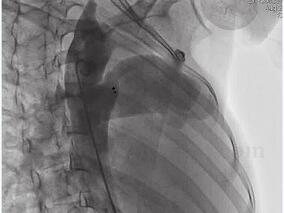

1小时条评论患者,女,17岁。因4个月前一过性头晕行超声心动图检查发现主动脉-肺动脉间存在异常血流,BP 120/80mmHg,心界不大,HR 80次/分,律齐,胸骨左缘第2、3肋间闻及3/6级收缩期吹风样杂音。可能是什么原因造成的?该如何补救? 【临床资料】 患者,女,17岁。入院前4个...